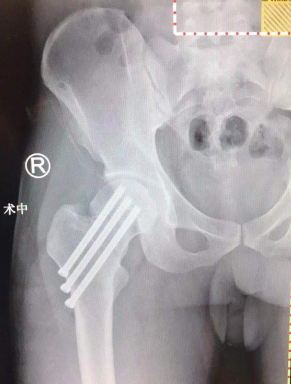

术后影像

2月2日,张传开主任郝亮闫成尚医生团队为患者进行骨科机器人导航下复位股骨颈骨折手术。患者被推进手术室,麻醉、连接机器人导航装置、术中C型臂透视、手法复位后,在骨科机器人导航下精准置入三枚空心螺钉进行骨折内固定,C型臂透视显示:螺钉位置与术前规划一致,固定效果可靠。手术仅花了50分钟,一气呵成,非常成功。术中出血量仅10ml,手术创口仅1厘米,术后几乎感觉不到疼痛,患者和家属都挺满意。

张传开主任介绍,传统骨科手术治疗股骨颈骨折难度高,需要切开复位钢板内固定,患者创伤大,术后并发症多;尤其是置钉位置,需要借助C型臂反复透视,依靠医生的空间想象和徒手操作确定螺钉置入方向,往往无法实现精确定位。采用机器人手术,定位、置钉更加精准,让手术医生有了“透视眼”,做到了“指哪打哪”,精确度误差控制在0.2毫米以内,实现了定位精准、软组织损伤小、手术切口小、手术安全性高的预期目标。整个手术过程中,透视次数大幅减少,对患者及医护人员的放射保护大大增强。